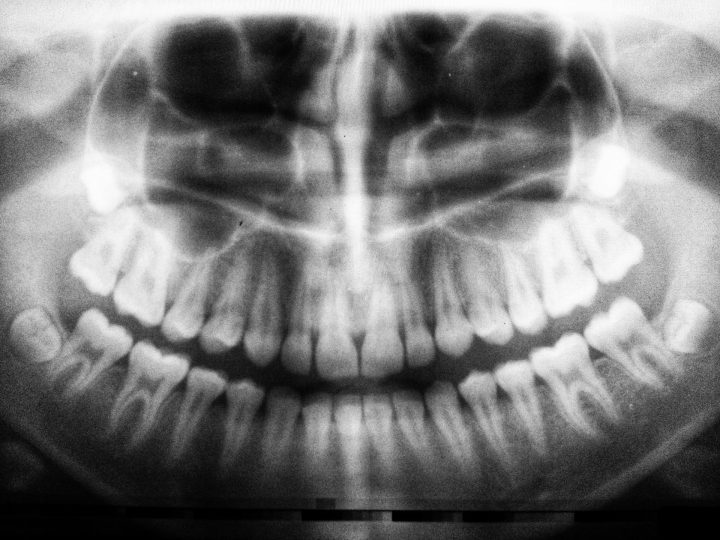

Braces are an orthodontic treatment that uses brackets, wires, and bands to shift teeth into their proper position. They are typically made from metal or ceramic and are attached to the teeth using a special adhesive. Braces gradually move teeth by applying constant pressure until they get to the desired position. Orthodontists adjust the brackets and wires every few weeks to ensure the teeth continue moving in the right direction.

Both braces and Invisalign are effective at straightening teeth, but they work in slightly different ways. Braces are better at treating complex orthodontic issues, such as severe overcrowding or bite problems. Invisalign is better suited to treating mild to moderate orthodontic issues like crooked or spaced teeth. Your orthodontist can advise you on the best treatment option for your needs.